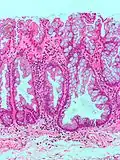

| Tubular Adenoma (Villous, Tubulovillous) | Colorectal | Tubular glands with elongated nuclei (at least low-grade atypia) | Yes | ![]() |

|

| Traditional serrated adenoma | Colorectal | Serrated crypts, often villous architecture, with cytologic atypia, eosinophilic cells | Yes | ![]() |

Serrated polyposis syndrome |